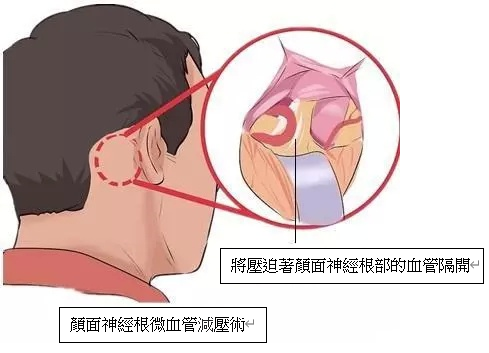

全身麻醉下, 脑神经外科医生会在显微镜下, 在病人耳后的颅底骨进行手术, 手术并不是在大脑内部进行操作,而是利用人体组织的间隙、在脑组织与颅骨之间的蛛网膜下腔内进行手术, 因此不需要破开任何脑神经。脑神经外科医生会将压迫着颜面神经根部的血管隔开,并以人造海棉(Teflon) 将血管与神经永久阻隔,去除神经线短路的因由。手术的治愈率达到80-90%上,复发率约10%,严重的并发症 (如听觉神经功能失聪) 的风险的发生率侧为2%。